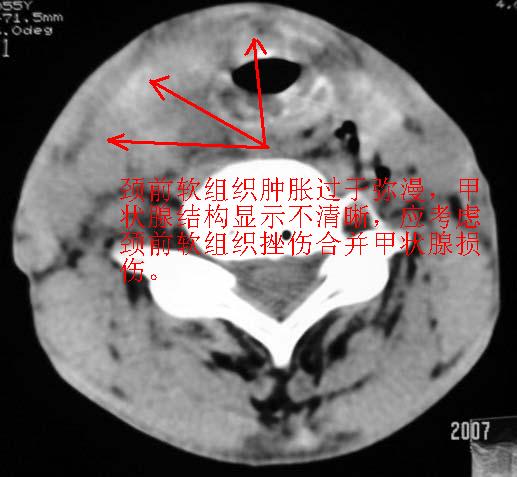

以下是引用dyqct在2007-4-20 16:19:00的发言:[br]考虑:1、左侧梨状窝区破裂伴左颈深、浅部气肿。[br] 2、右侧甲状腺区血肿(请追问病史是否伤及右颈部)。[br] 3、建议病情稳定后增强扫描除外右侧甲状腺腺瘤。